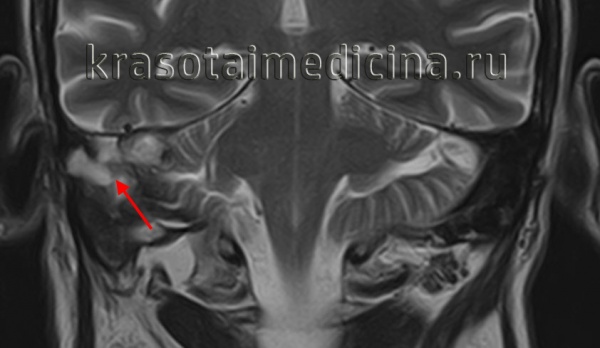

КТ анатомия сосцевидного отростка: особенности и показания